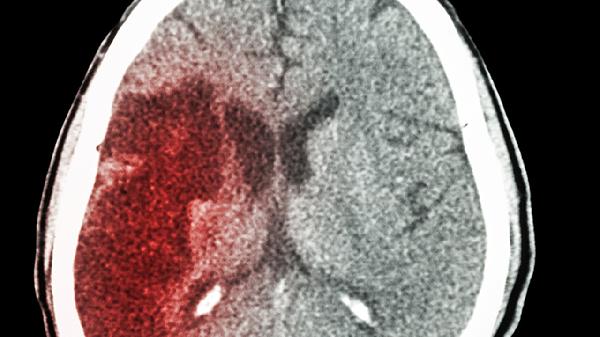

深夜的急诊室总是上演着各种惊心动魄的故事,而64岁老张的故事尤其让人警醒。原本身体硬朗的他,某天晚饭后像往常一样躺在沙发上看电视,突然发现左手使不上劲,说话也开始含糊不清。送到医院确诊为脑梗,虽然保住了性命,却留下了半身不遂的后遗症。医生那句“晚饭后的几个习惯可能是诱因”,让家属后悔莫及。

突然出现的头晕目眩、单侧肢体麻木、说话不清、剧烈头痛等,都可能是脑梗前兆。记住“FAST”识别法:Face(面部下垂)、Arm(手臂无力)、Speech(言语障碍)、Time(抓紧时间送医)。